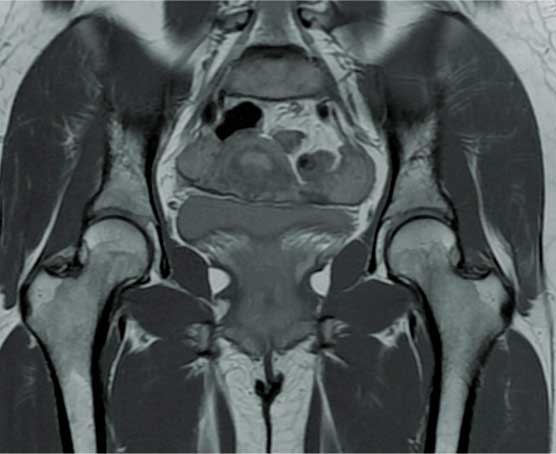

Está indicada en un paciente adulto joven para diagnosticar y tratar con certeza problemas de bloqueo en la cadera, extracción de cuerpos libres intrarticulares, rupturas de labrum, lesiones del cartílago y choque femoroacetabular.

Es la pérdida de la continuidad del tejido óseo en la articulación de la cadera, producidas por caídas o traumatismos de alta energía, la cual se caracteriza por dolor intenso, incapacidad funcional, chasquidos, acortamiento y rotación de la pierna, el diagnóstico definitivo es por radiografía o tomografía.